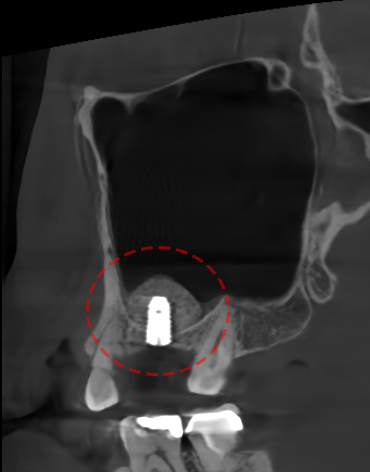

다만, 이 과정에서 잔존골을 평가하여

픽스처 식립이 가능하다고 판단되면,

상악동 거상술을 통한 골이식과 동시에

임플란트를 식립하는 경우도 있습니다.

5. 술 후 관리의 필요성

사진을 보면 상악동 거상술이

잘 마무리된 것이 확인됩니다.

충분한 공간이 확보되어

상악동에는 큰 영향이 없이

픽스처가 자리 잡고 있습니다.

이렇게 식립된 픽스처는 골유착을 위해

철저한 관리가 필요합니다.

수술 후 세균에 의해 감염이나

또는 염증이 생기는 경우에는

천공과 같은 합병증으로 이어지고

골유착이 이뤄지지 않을 수 있습니다.